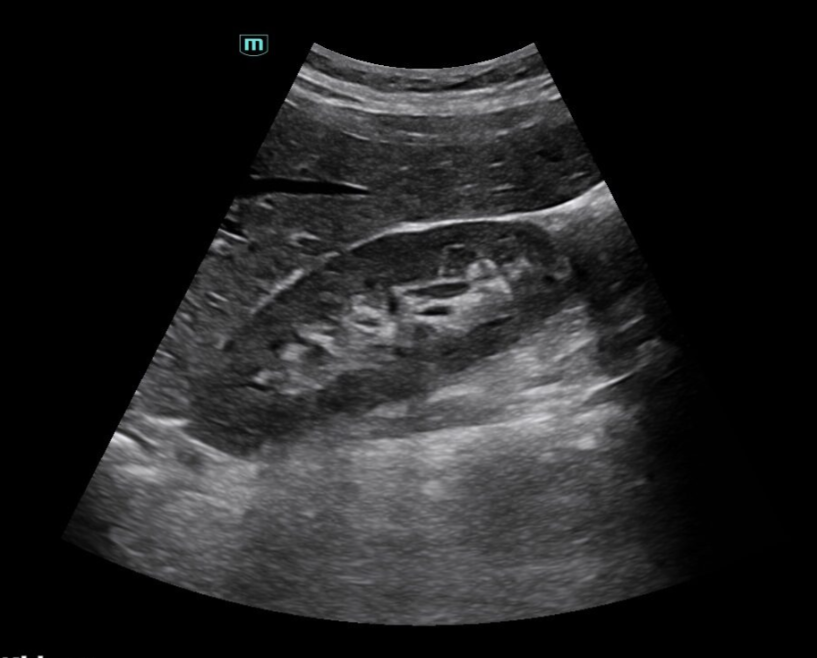

Ultrasound imaging is not only used during pregnancy but also to examine solid organs and tissues throughout the body. It can help detect early stages of many illnesses, including cancer. Ultrasound is commonly used to diagnose gallstones, investigate causes of infections and heavy or painful periods, assess issues with the testes, and determine the nature of soft tissue lumps and bumps.